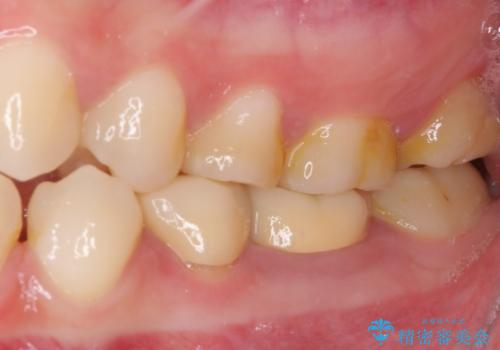

- クラウンを装着したばかりの歯の歯肉が腫れていることを気にして来院された患者様です。

むし歯がとても大きく、歯茎に歯の一部が埋もれてしまっているため、汚れが溜まりやすくなっている状態でした。

根歯の挺出(歯を引っ張り出す部分矯正)、歯周外科処置などを行った後、オールセラミッククラウンにて補綴することとしました。